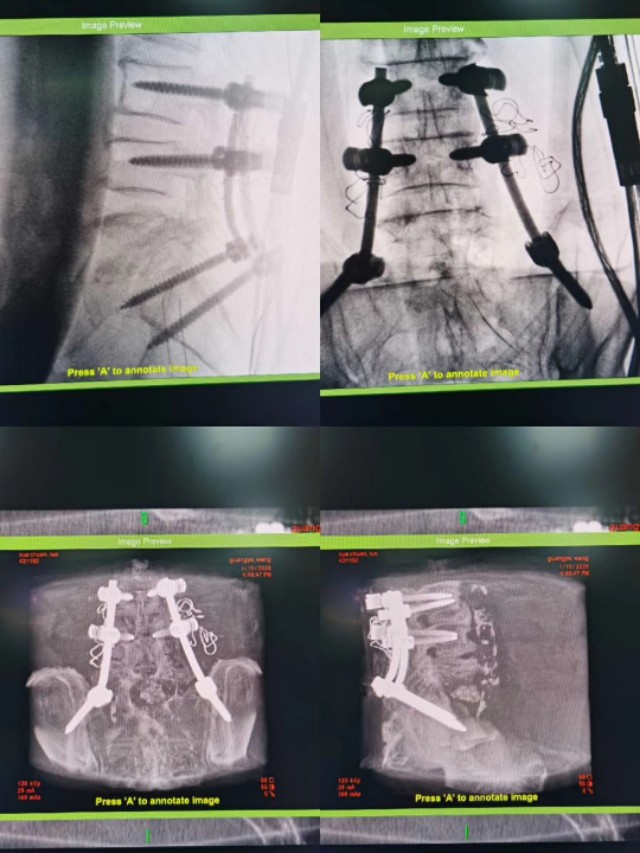

老人牙齿不好引起腰椎原发性腰5骶1化脓性感染,侵犯至椎管内,伴神经压迫。显微镜微创通道加导航辅助微创通道下间隙内感染清除,经微创入路行腰3腰4及导航下精准植入髂骨钉,钉道理想。深圳华大基因确诊细菌来源于牙齿������,术后一个月复查,病人己完全康复������